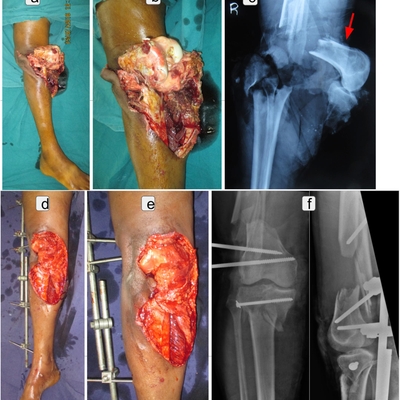

Click on an image below to view more info.